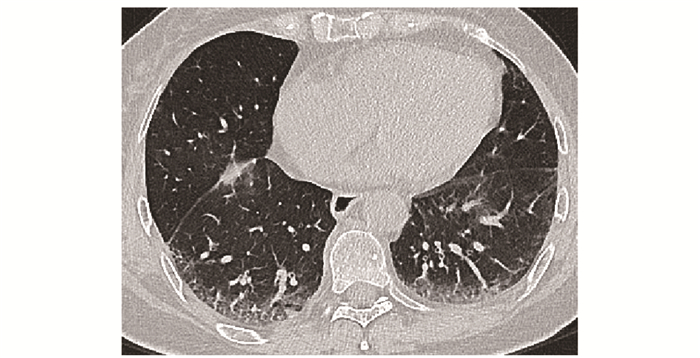

• 摘要: 结缔组织病累及呼吸系统可表现为间质性肺疾病、弥漫性肺泡损伤、肺泡出血、肺血管病变、胸膜病变及气道病变等。其临床表现缺乏特异性, 肺功能和胸部CT是最常用的检查手段。不同结缔组织病累及呼吸系统的影像特征具有相似性, 但又各具特点。本文就结缔组织病呼吸系统受累相关影像表现进行概述, 以提升读者的认知并指导临床实践。

Abstract: Respiratory manifestations of connective tissue diseases include interstitial lung diseases, diffuse alveolar injury, alveolar hemorrhage, pulmonary vascular lesions, pleural lesions and airway disease. Their clinical symptoms were not specific. Pulmonary function test and chest computed tomography come to be the most frequently applied examinations. Different connective tissue diseases involving respiratory system have not only common features but also characteristic imaging patterns. In this paper, imaging manifestations of respiratory diseases associated with connective tissue diseases were reviewed, so as to improve readers' recognition of the diseases and guide clinical practice.